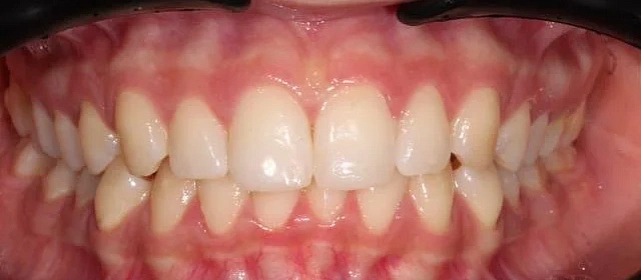

Зубы выровнены, скученность устранена, линия смыкания нормализована. Установлены несъёмные ретейнеры на обе челюсти, сняты слепки для ретенционных кап.

Решение: Поставили элайнеры Click на обе челюсти. Начали с 32 кап, но случай потребовал три дозаказа: 30, 10 и 10 кап — итого 82 капы за 30 месяцев. Количество дозаказов объясняется и сложностью случая (скученность плюс деформация кривой Шпее), и тем, что контрольные визиты были реже обычного из-за проживания за границей. Тем не менее результат достигнут: зубы ровные, смыкание в норме. На ретенцию пациентка приехала отдельно — зафиксировали ретейнеры на обе челюсти, сняли слепки для ретенционных кап.

Сложный случай: скученность на обеих челюстях плюс деформация кривой Шпее — жевательные зубы на разной высоте. Дополнительный вызов — пациентка живёт за рубежом, визиты реже, контроль сложнее. Три дозаказа — много, но каждый был обоснован: основной набор расширил дуги и убрал основную скученность, дозаказы последовательно довели смыкание до нормы. 82 капы за 30 месяцев — результат получен.